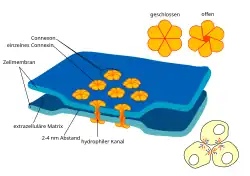

Diese kanalbildenden Proteinkomplexe sind ein Verbindungstyp, über den die Perizyten mit den Endothelzellen verbunden sind.

Die Perizyten sind fest mit den Endothelzellen verankert. Mindestens drei Arten von Perizyt-Endothel-Kontakten bilden dabei die Verbindung zwischen diesen beiden Zelltypen. Dies sind Gap Junctions (kanalbildende Proteinkomplexe), fokale Adhäsion (Adhesion Plaques) und Peg-and-Socket-Invaginationen.[34] Die Gap Junctions verbinden dabei die beiden Zytoplasmen direkt miteinander und ermöglichen über Kanäle den Austausch von Ionen und kleineren Molekülen zwischen den beiden Zelltypen.[39] Über die fokale Adhäsion sind die Perizyten mit den Endothelien mechanisch fest verankert.[40] Die Peg-and-Socket-Invaginationen bestehen aus wechselseitig verflochtenen Ausstülpungen der beiden miteinander verbundenen Zellen.[41] Auch dieser Zellkontakttyp trägt offensichtlich zur mechanischen Verankerung der Perizyten auf den Endothelien bei.[34]